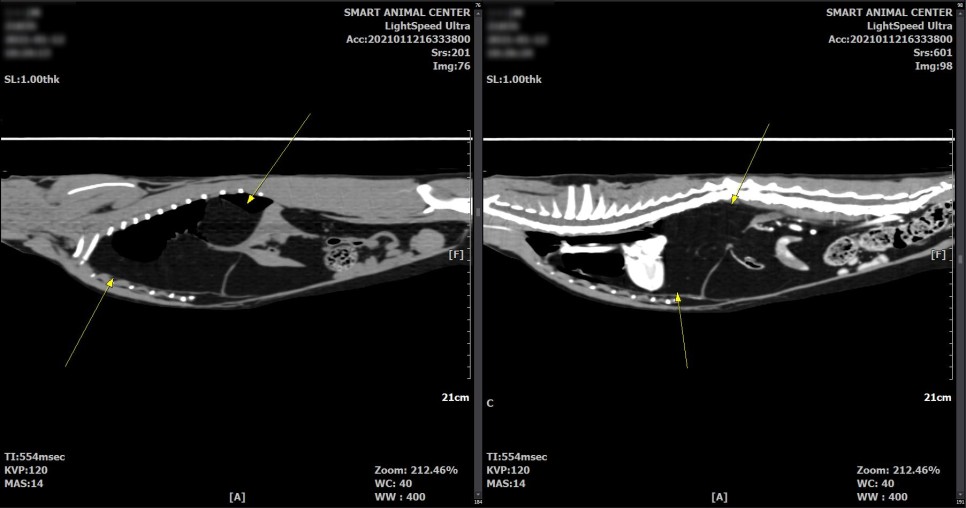

보다 면밀한 흉부 평가를 위해서 CT촬영을 실시했습니다.

CT 검사 결과

횡격막의 일부 결손 부위와 흉강 내 다량의 지방 병변이 확인되었습니다.

횡격막 결손부에 의한 다량의 지방 디스크가 있을 수 있으며,

또한 영상학적으로 악성도를 지시하는 것과 같은 소견은 관찰되지 않았습니다.

다량의 지방으로 폐 실질 등, 왼쪽 변위가 유발되고 있다고 판단되었습니다.